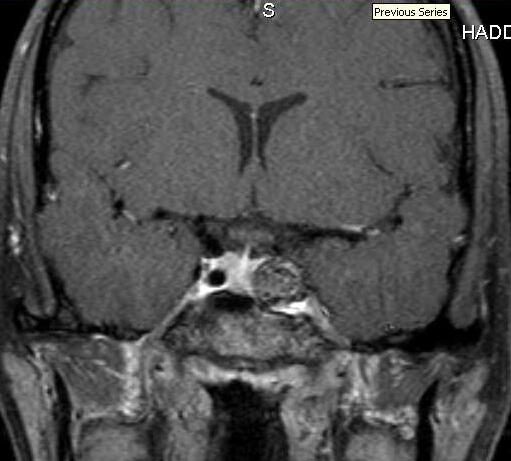

Coiled Aneurysm with IC Occlusion - SP32-20061216 - 015

Title Coiled Aneurysm with IC Occlusion - SP32-20061216 - 015

Subject Aneurysm; Occlusion

Description Imaging of coiled aneurysm with IC occlusion.